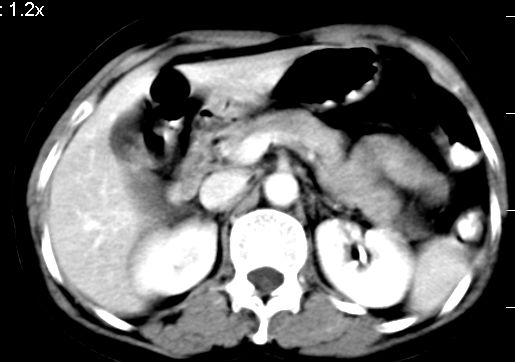

标题: CT10752:F,52岁,反复上腹部疼痛,平扫+增强. [打印本页]

f、52岁,反复上腹部疼痛2年。肺结核病史10多年,胸片双上肺结核纤维化。

ct表现:

肝大小形态未见异常,肝内外胆管无扩张,肝s8段见一动脉期明显血管样强化结节,门脉期呈高密度,延迟期呈等密度,胆囊不大,增强扫描见胆囊及胆囊颈管壁增厚,有强化。

双肾灌注良好,代谢增快,动脉期肾盂见造影剂,左肾下极背侧见一略低密度病灶,延迟期见似不强化囊肿,双侧肾上腺未见异常。

胰腺及脾未见异常。肾门水平腹膜后见小淋巴结。腹腔未见积液征象。

诊断:

1、胆囊炎(轻度)。

2、肝s8段结节,考虑小血管瘤。

3、左肾下极低密度灶,考虑囊肿可能性大,建议随访,除外小肾癌(无强化可以基本除外)。

4、目前ct表现尚不能解释患者上腹部疼痛,建议上消造影检查,除外胃炎等疾患。